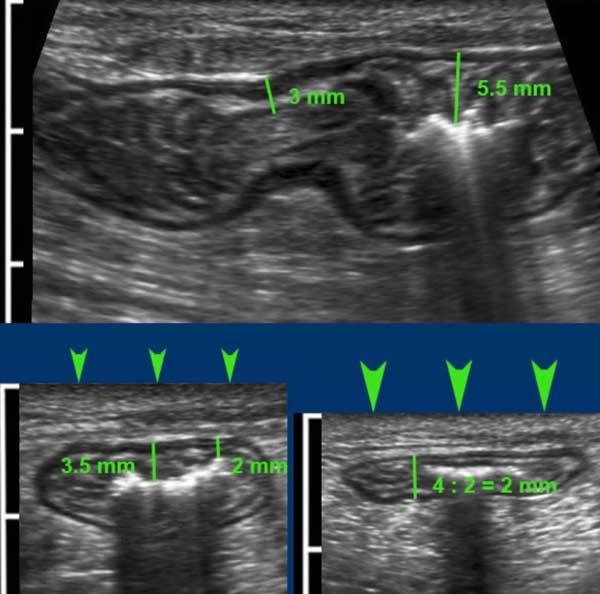

Ngược lại với hầu hết các quai ruột bệnh lý, các quai ruột non bình thường có thể bị ép xẹp tốt trong thì giãn nghỉ.

So sánh hồi tràng bình thường (trái) và hồi tràng trong bệnh Crohn (phải), không nén (hình trên) và có nén (hình dưới).

Note the same cm-scale in all four US-images.

Độ dày thành đơn ở người bình thường là 1,5 mm, ở bệnh nhân Crohn là 6,5 mm